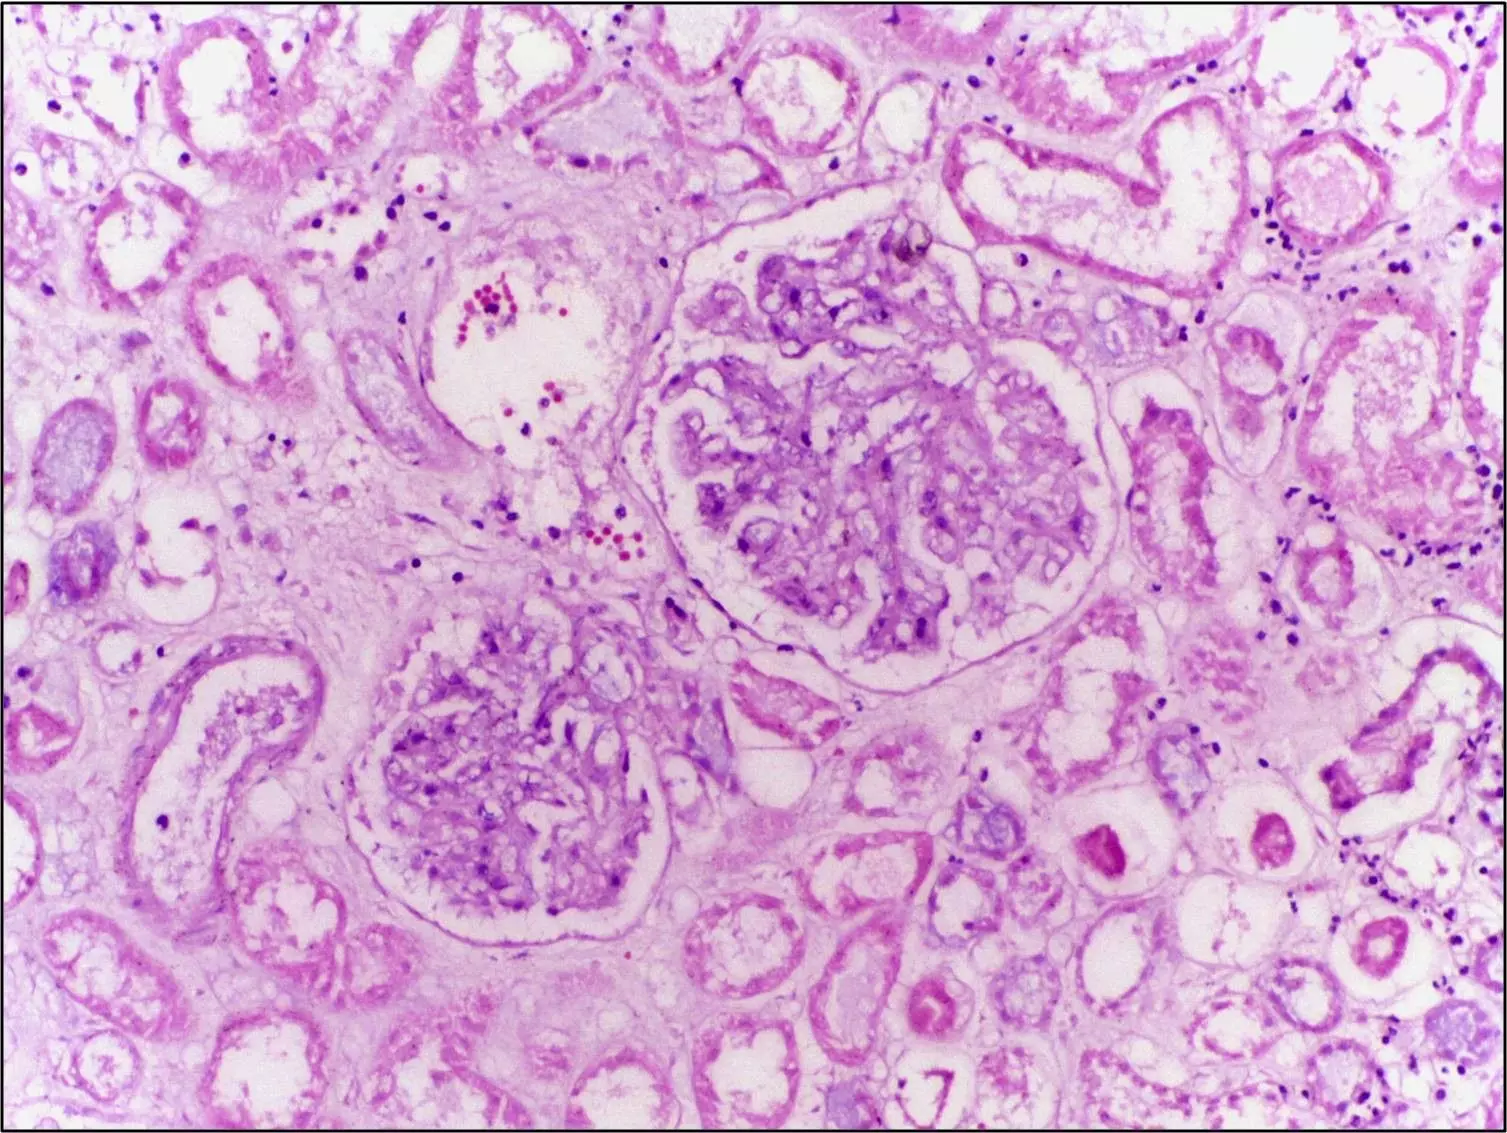

1. An Introduction to Pathology